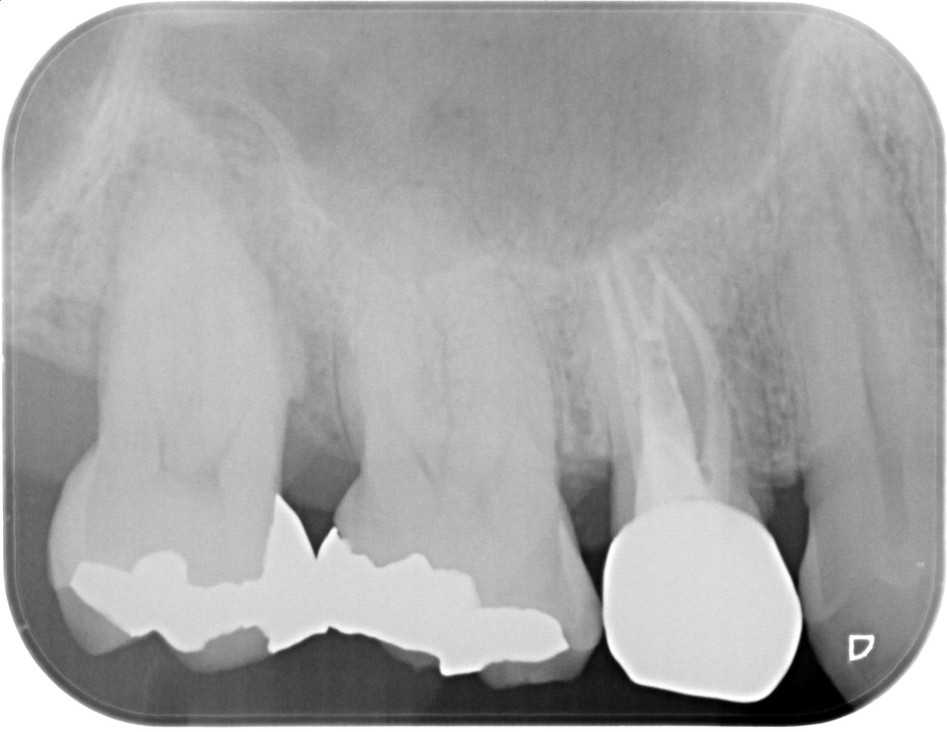

症例3

| 項目 | 詳細 |

|---|---|

| 患者様データ | 40代 女性 |

| 来院時の主訴 | 「右上の奥歯を抜歯と言われてしまった。」 |

| 医院の診断 | 虫歯の再発、慢性根尖性歯周炎 |

| 通院期間 | 10ヶ月 |

| 来院回数 | 21回 |

| 治療費 | 1,140,000円(税抜) 《内訳》 精密感染根管治療80,000円(小臼歯)+100,000円(大臼歯)×3、ファイバーポストコア20,000円×4、セラミック治療120,000円×5+80,000円 |

| リスクと副作用 | ①根管治療歯は長期的には破折するリスク ②メインテナンスが必要 |

| ココがこだわりのポイント☝ |

ラバーダム防湿とマイクロスコープを使用して丁寧に治療を行いました。 再根管治療のため、殺菌性があり歯を補強することのできる根管充填材料を使用しています。 |